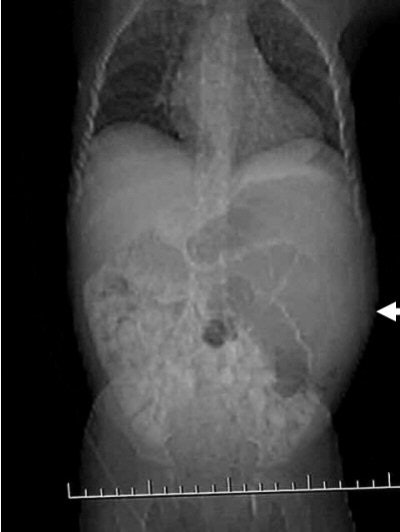

Case 1: The patient is a three-year-old black female who appears to be in no distress. The mother stated that she was giving the child a bath and noticed that her abdomen looked distended, and harder on the left side than the right. All the child’s labs are normal, and there is no family history of medical problems.

In Figure CT 9, the scout film shows a gaseous abdomen with displacement of bowel contents towards the right lower quadrant.

Axial images (Figures CT 10 and CT 11) show a mass beginning just below the kidneys on the left side and extending almost through the pelvis. The child was diagnosed with Wilm’s tumor of the left kidney.